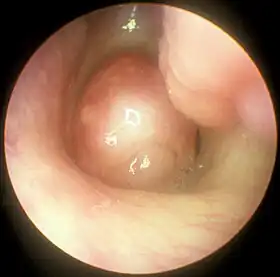

![]() Large nasal polyp (round mass, center), which is commonly treated and removed by FESS | |

Functional endoscopic sinus surgery is most commonly used to treat chronic rhinosinusitis (CRS),[8] only after all non-surgical treatment options such as antibiotics, topical nasal corticosteroids, and nasal lavage with saline solutions[9] have been exhausted. CRS is an inflammatory condition in which the nose and at least one sinus become swollen and interfere with mucus drainage.[9] It can be caused by anatomical factors such as a deviated septum or nasal polyps (growths), as well as infection. Symptoms include difficulty breathing through the nose, swelling and pain around the nose and eyes, postnasal drainage down the throat, and difficulty sleeping.[10] CRS is a common condition in children and young adults.[11]

The purpose of FESS in treatment of CRS is to remove any anatomical obstructions that prevent proper mucosal drainage. A standard FESS includes removal of the uncinate process, and opening of the ethmoid air cells and Haller cells[12] as well as the maxillary ostium, if necessary. If any nasal polyps obstructing ventilation or drainage are present, they are also removed.[8] In the case of paranasal sinus/nasal cavity tumors (benign or cancerous), an otolaryngologist can perform FESS to remove the growths, sometimes with the help of a neurosurgeon, depending on the extent of the tumor. In some cases, a graft of bone or skin is placed by FESS to repair damages by the tumor.[13]